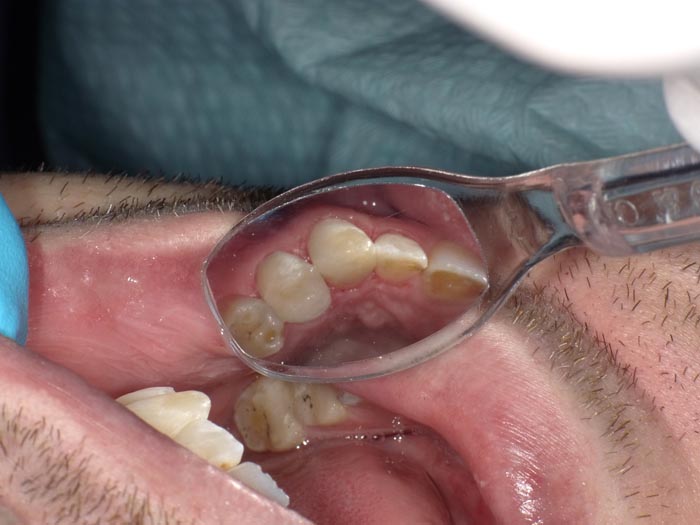

Case 1

A 37-year-old patient presented for treatment after years of neglect. After administering anesthetic and placing an Isolite isolation device, we prepared teeth #10–12 and restored them

with Activa Bioactive-Restorative composite.